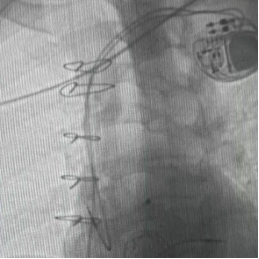

永久起搏器植入術“這相當于用微創的方式,完成過去需要三次手術才能解決的問題。”陳文生主任解釋說,介入操作無需再次開胸,只需通過血管穿刺送入導管,對患者創傷小,尤其適合這種多次手術后的高危患者。

手術臺上,心臟大血管外科陳文生團隊通過細致的影像引導,將球囊送至原有瓣膜處進行擴張,隨后將新的生物瓣精準釋放在預定位置 。最后,在心臟穩定的狀態下,順利植入了永久起搏器。整個過程中,患者生命體征平穩。

術后超聲顯示,李爺爺三尖瓣的返流量從“大量”降至“少量”,心臟血流得到根本改善。起搏器工作正常,心跳恢復穩定節奏。術后恢復順利,水腫等癥狀明顯消退,恢復情況良好。目前,李爺爺已康復出院。